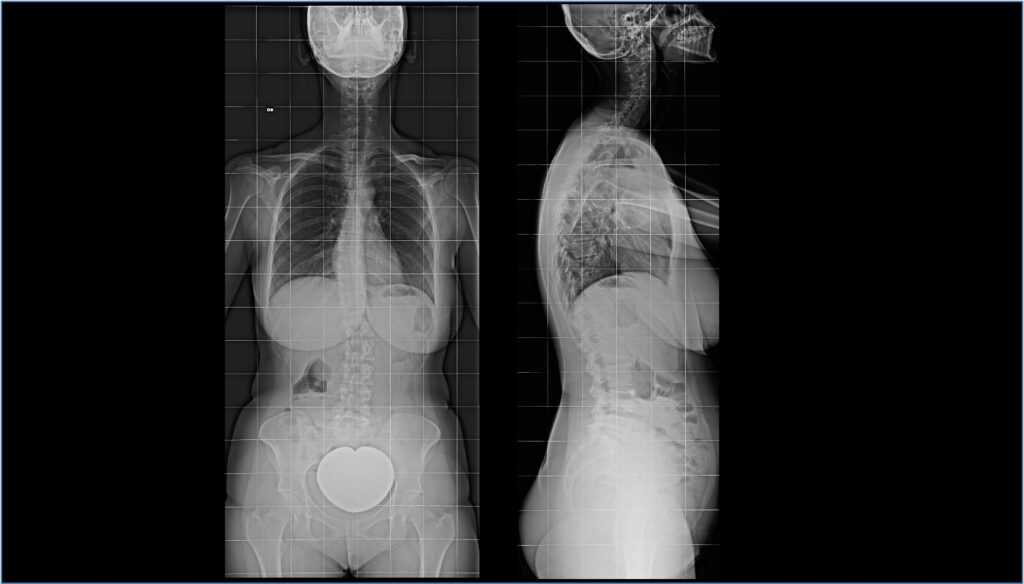

RX colonna vertebrale in toto

Cos’è? La radiografia della colonna vertebrale in toto o completa, permette di ottenere un’unica immagine dell’intera colonna vertebrale, dalla cervicale al bacino, e di visualizzare